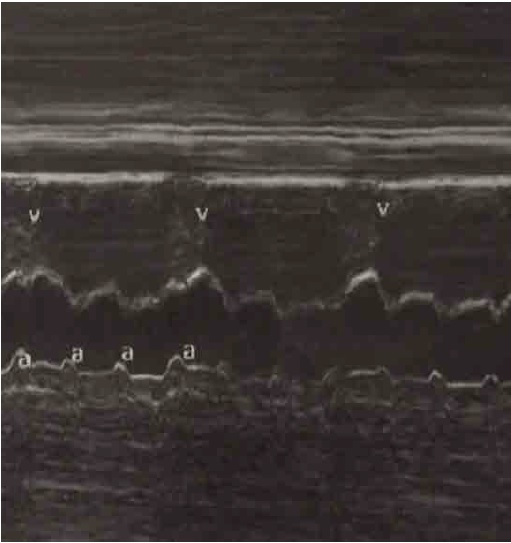

Al ingreso al HUCSR se realizan pruebas de bienestar fetal las cuales son normales; posteriormente se realiza ecografía de detalle en la cual no se observan signos de hidrops fetal ni otras alteraciones anatómicas. Finalmente, se realiza ecocardiograma fetal donde se encuentra situs solitus, situs vascular normal, eje cardiaco de 45º, relación cardiotorácica de 0,55, corte de cuatro cámaras normal, concordancia auriculoventricular y ventriculoarterial, inserción valvular normal, foramen oval permeable, flujo hacia aurícula izquierda, movimientos de paredes libres de ventrículos de amplitud normal; se observa imagen hiperecogénica a nivel del nodo sinoauricular sugestiva de fibroelastosis endocárdica (figura 1). No se evidencia ritmo sinusal, se documenta disociación auriculoventricular en Modo M ((figure 2), con frecuencia cardiaca ventricular de 50 lpm y frecuencia auricular de 135 lpm, segmentos PR variables, e istmo aórtico con flujo anterógrado. No hay evidencia de disfunción diastólica dada por ductus venoso normal.